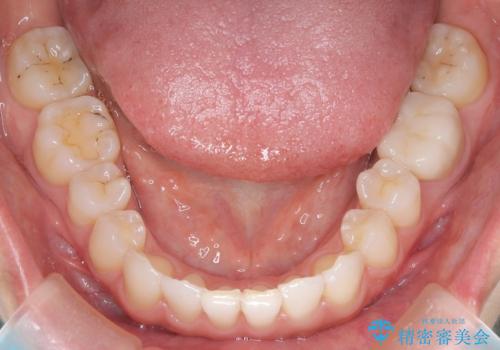

- 前歯のガタガタを主訴に来院されました。

叢生の量は軽度でしたが臼歯の遠心移動を行い、インビザラインにて治療をしました。

叢生の改善に必要なスペースは遠心移動やIPRで作ることが可能です。今回は遠心移動をメインにスペースを作って叢生の改善を行いました。